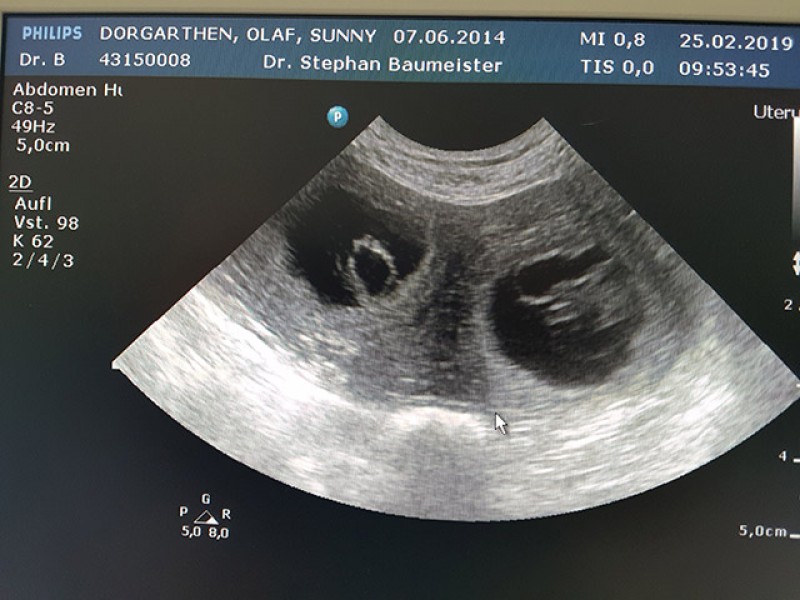

Über den weiteren Verlauf werde ich weiter berichten...aber hier einmal ein frühes Foto von 2 Babys, die zum jetzigen Zeitpunkt so groß sind wie Gummibärchen. Mittig unterhalb der Beiden konnten wir auf einer anderen Einstellung noch eine 3. Anlage ( 3 auf einem Bild ) sehen...die ganze Aufnahme war aber zu unscharf zum Ausdrucken.